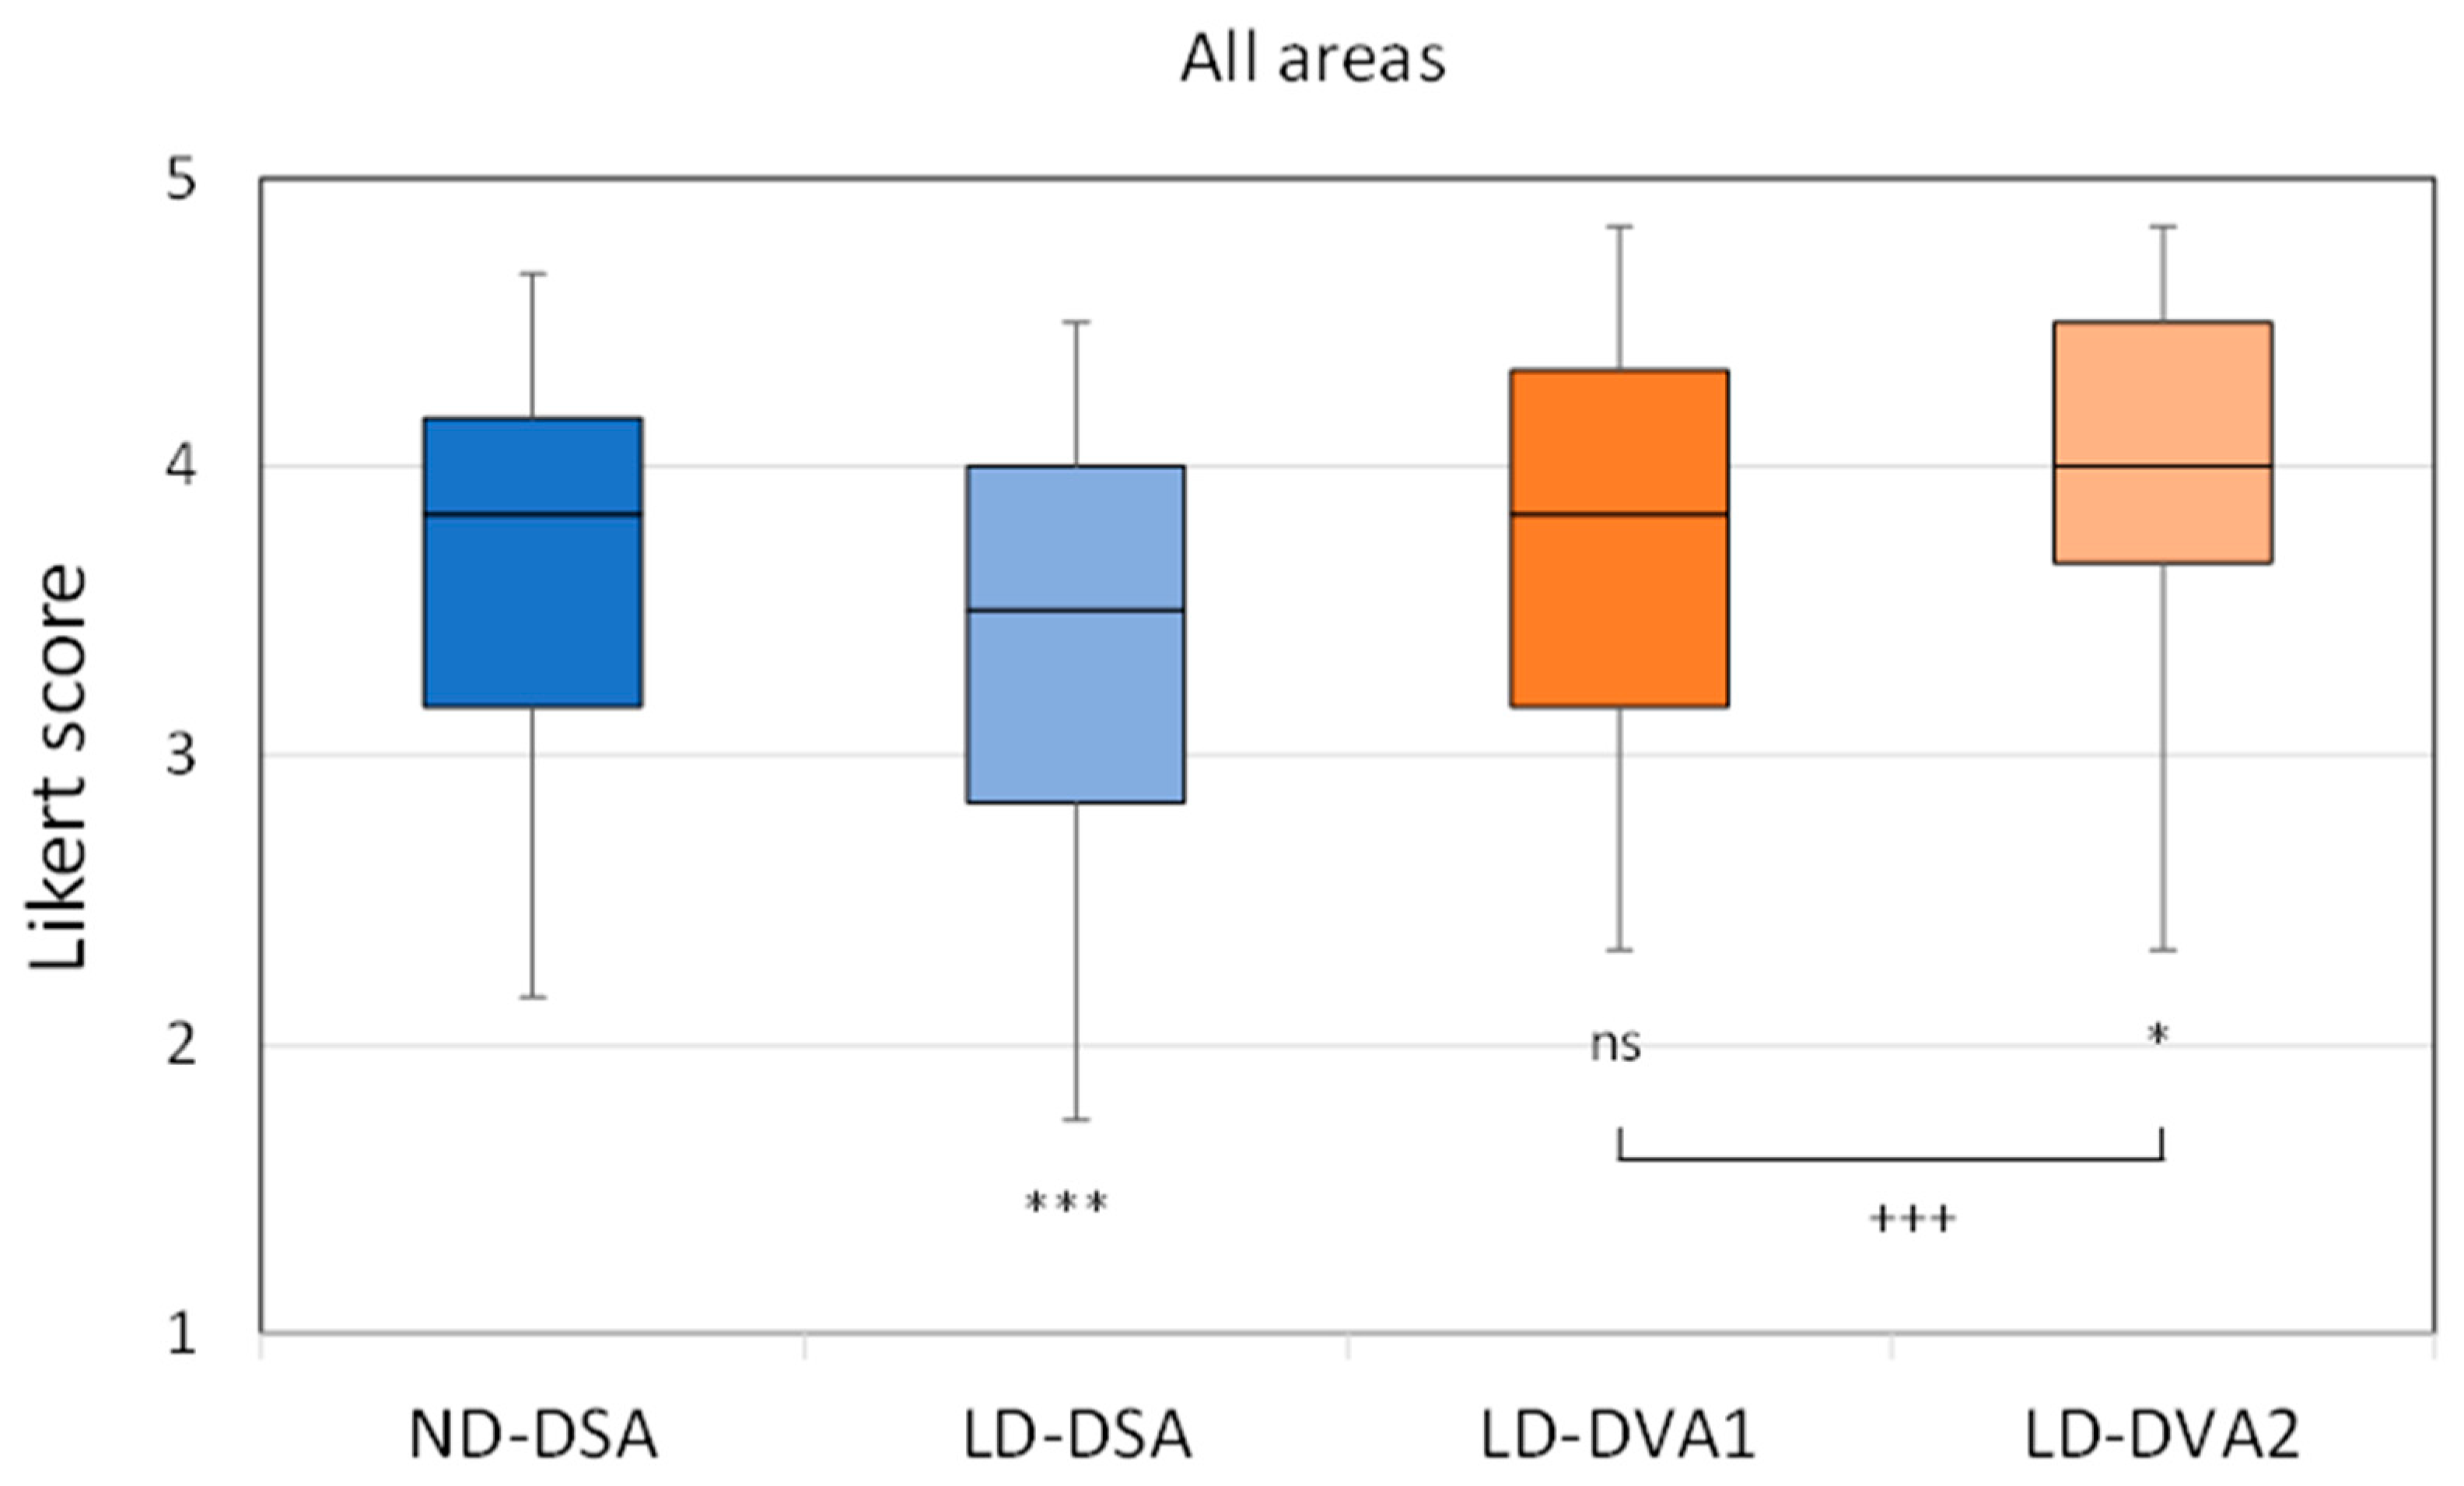

3.3. Visual Evaluation

| ND-DSA | LD-DSA | LD-DVA1 | LD-DVA2 | p (DVA1 vs. DVA2) | ||

|---|---|---|---|---|---|---|

| All | Median(SQR) | 3.83 (1.00) | 3.50 (1.17) | 3.83 (1.17) | 4.00 (0.83) | <0.001 |

| p (vs ND-DSA) | <0.001 | >0.999 | 0.028 | |||

| Mean ± SEM | 3.68 ± 0.05 | 3.35 ± 0.05 | 3.69 ± 0.05 | 3.89 ± 0.04 | ||

| Aortoiliac | Median(SQR) | 4.33 (0.66) | 4.00 (0.50) | 4.33 (0.54) | 4.33 (0.50) | 0.55 |

| p (vs ND-DSA) | 0.118 | >0.999 | >0.999 | |||

| Mean ± SEM | 4.20 ± 0.07 | 3.94 ± 0.06 | 4.21 ± 0206 | 4.24 ± 0.06 | ||

| Femoral | Median(SQR) | 4.16 (0.5) | 3.83 (0.66) | 4.17 (0.79) | 4.33 (0.50) | <0.001 |

| p (vs ND-DSA) | <0.001 | >0.9999 | 0.2024 | |||

| Mean ± SEM | 4.19 ± 0.05 | 3.79 ± 0.07 | 4.18 ± 0.06 | 4.35 ± 0.04 | ||

| Popliteal | Median(SQR) | 3.58 (1) | 3.17 (1.16) | 3.67 (0.87) | 4.00 (0.79) | <0.001 |

| p (vs ND-DSA) | 0.2711 | 0.1191 | <0.001 | |||

| Mean ± SEM | 3.41 ± 0.09 | 3.19 ± 0.09 | 3.67 ± 0.08 | 3.89 ± 0.08 | ||

| Talocrural | Median(SQR) | 3.41 (1.00) | 2.83 (1.00) | 3.17 (1.00) | 3.67 (1.00) | <0.001 |

| p (vs ND-DSA) | <0.001 | 0.8736 | ||||

| Mean ± SEM | 3.22 ± 0.08 | 2.7 ± 0.10 | 3.13 ± 0.08 | 3.44 ± 0.07 |